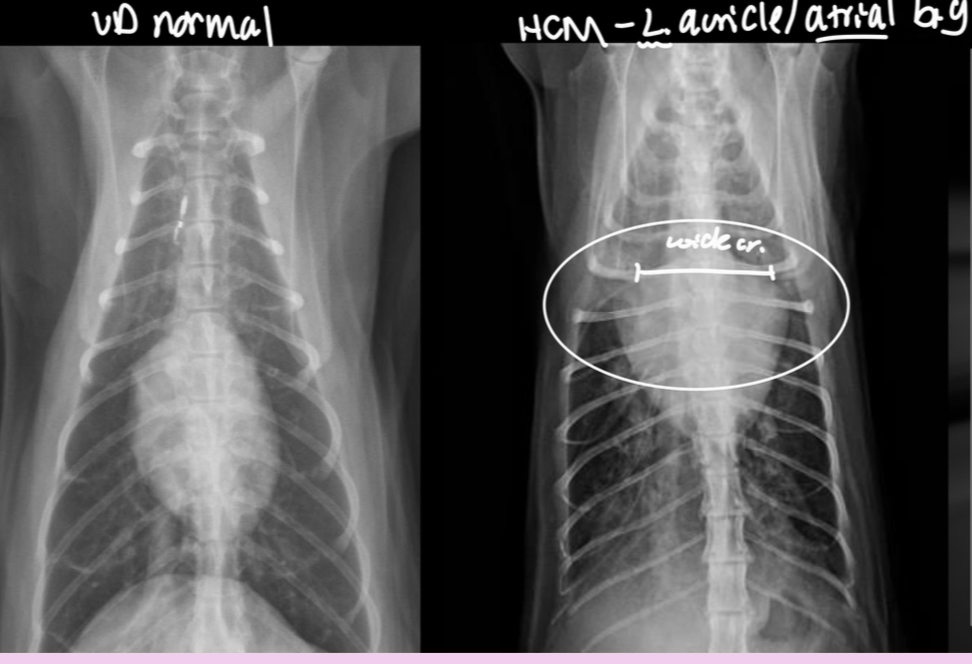

3 features of LAE on DV

-double opacity sign

-separation of main stem bronchi

-LA bulge at 2:30-3 o’clock

What part of the heart is enlarged

LAE